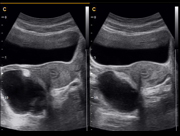

Ovarian Dropsy 2B Mode

Fetus,2B Mode